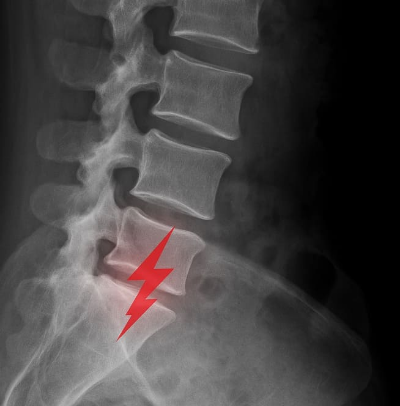

요통 원인과 요통 증상은 단순한 허리통증으로 넘기기 쉽지만, 때로는 심각한 척추질환의 전조일 수 있습니다. 반복되는 요통 증상에 시달리거나, 원인을 알 수 없는 허리 통증이 지속된다면 정확한 요통 원인을 파악하고 맞춤형 치료가 필요합니다. 이 글에서는 요통 원인과 요통 증상을 중심으로 자세히 설명하고, 올바른 대처 방법과 예방법, 병원에 가야 하는 시점 등을 다루어 건강한 허리를 지키는 데 도움을 드리겠습니다.

요통은 허리 부위에 발생하는 불편감이나 통증을 통칭하는 말입니다. 단순한 피로로 인한 뻐근함부터, 움직이지 못할 정도의 극심한 통증까지 요통 증상의 범위는 매우 다양합니다. 특히 현대 사회에서는 장시간 앉아 있는 직장인, 무거운 짐을 자주 드는 근로자, 스마트폰 사용 시간이 긴 청소년 등 누구나 요통 원인에 노출되어 있습니다. 요통 증상은 일시적인 근육통으로 나타나기도 하지만, 반복적이거나 지속적인 통증은 반드시 원인을 정확히 파악해야 합니다. 요통 원인을 방치하면 만성 통증으로 이어지며 삶의 질을 떨어뜨릴 수 있기 때문입니다.

- X-ray: 척추 구조 이상 확인

- MRI: 디스크 탈출, 협착 여부 확인

- CT: 정밀한 뼈 구조 분석